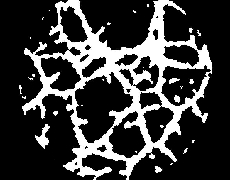

De cada una de las imágenes (ver Fig.3) se pueden extraer una serie de parámetros consensuados como significativos en los procesos angiogénicos. En todas las imágenes se puede observar la presencia de canales (cerrados y abiertos) de diferentes longitudes y con su característica intrínseca de linealidad, células aisladas, grumos de células, fondo de textura uniforme y un halo circundante de mayor brillo que es una interferencia incorporada por condiciones de contorno en la adquisición. El procesamiento individual se puede dividir a su vez en 3 partes: 1) pre-procesamiento, 2) realce de las morfologías de interés, y 3) post-procesamiento.

El siguiente procedimiento es aplicar un proceso de binarización (ver Fig.11), seguido de otro de esqueletonización (ver Fig.12), de forma que quedan perfectamente delineados los canales detectados. En la figura 13 se puede observar la superposición de la imagen resultantes del pre-procesamiento (paso 1) y del procesamiento (paso 2); se marcan en negro los canales conectados y en blanco los canales aislados (no conectados).

Figura 11. Binarización Figura 12. Esqueletonización

Figura 13. Superposición de imagen con trazado de canales detectados.